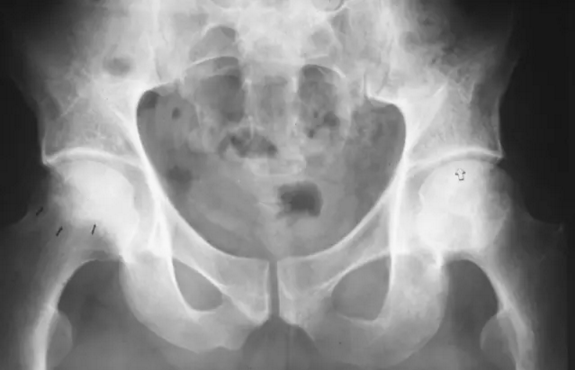

在股骨头缺血性坏死患者的骨盆正位平片可见不对称关节间隙狭窄(箭头),近关节硬化,软骨下囊肿形成围绕右髋继发退行性骨关节病。